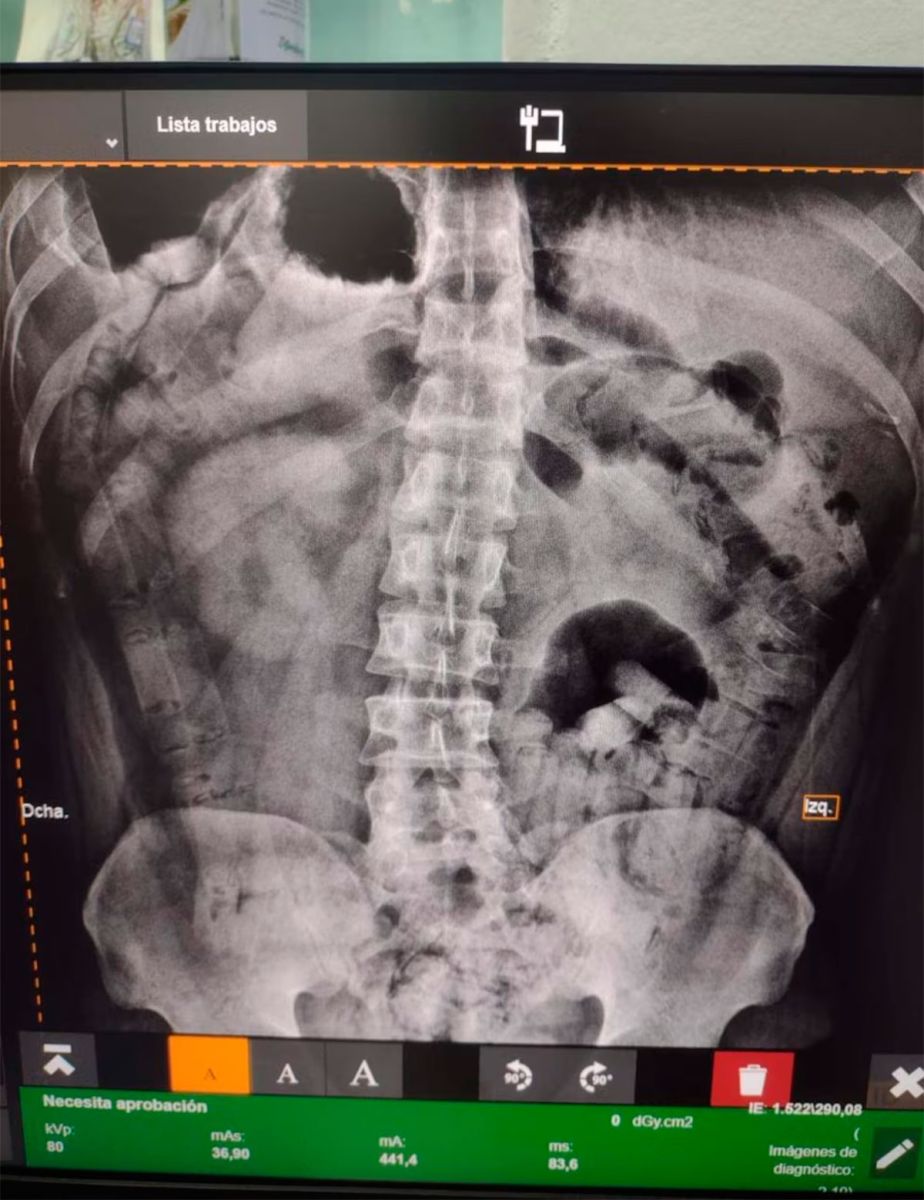

Radiografía de una mula Radiografía de una mula

Los casos recientes son casi idénticos.

Después de vomitar una cápsula, N. M., una mujer salteña de 20 años, ingresó de urgencia al Hospital San Vicente de Paul, en Orán, en la noche del 16 de marzo de este año. Tenía un fuerte dolor estomacal, náuseas y vómitos, según comentó a los médicos de guardia.

La sometieron a una cirugía y le sacaron del cuerpo 41 envoltorios con cocaína, con un peso de 465 gramos. Lo que estaba pasando llegó a oídos del personal policial de guardia en el centro de salud. Dieron aviso a la fiscalía de turno, que abrió una causa e imputó a la paciente.